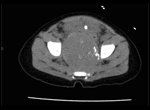

CT Scan of Pelvis

A computed tomography (CT) scan of the abdomen and pelvis was obtained (Figure 1). This revealed a large retroperitoneal pelvic mass left of midline with calcified densities.

Dr. Roger K. Harned: In the setting of a clinically palpable mass, a CT scan of the pelvis was obtained. This was performed with administered intravenous and oral contrast material with limited non-contrast-enhanced images of the pelvis. The examination showed a 4.8-cm (craniocaudual) X 5.2cm (anteroposterior) X 4.6-cm (transverse) soft-tissue mass filling the lower pelvis, anterior to and inseparable from the sacrum with some protrusion into the left sacrosciatic notch. The bladder, containing a Foley catheter, was displaced anteriorly and superiorly by the mass. There was no bony erosion or expansion of the sacral foramina, and the sacrum was normally formed without cleft or segmentation anomaly.

The mass was of soft-tissue density, contained scattered punctate and linear calcifications, and enhanced homogenously after administration of intravenous contrast material. There were no associated fluid collections, and the mass contained no fat density material. The retroperitoneum was free of mass or adenopathy; adrenal glands were normal; and the liver enhanced homogeneously without evidence of metastatic disease.